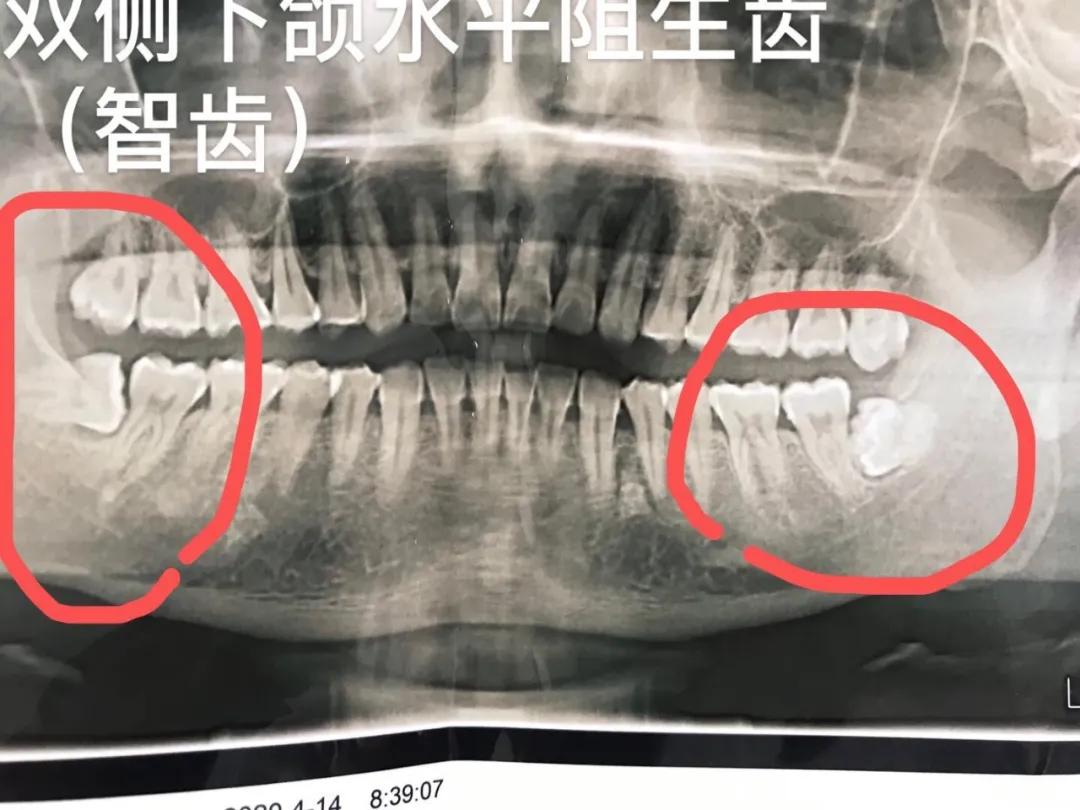

女同胞怀孕是人生中一个非常重要的时期,无论孩子还是母亲都需要重点保护,本身这个时期身体抵抗力低下,平时的一些疾病非常容易发病,特别是牙病,疼起来让人难以忍受,而治疗起来又非常麻烦,需要治疗很多次。口腔科的用药很多,虽说理论上治疗问题不大,但是实际中绝大多数患者为了孩子不愿意冒风险,所以在备孕前女同胞们最好把牙齿问题先解决掉,尤其是智齿问题。

怀孕期间由于体内雌激素水平增高,牙龈非常容易出血,如果自身口腔卫生不注意,牙龈就会增生肿大,出血剧烈,严重影响正常的生活。由于身体抵抗力低,智齿冠周炎的发病率极高,此时患者会出现牙龈肿大,面部肿大,颌下淋巴结肿大,严重的张不开嘴和发热,影响到正常的生活。

4.各类阻生牙(智齿)、儿童埋伏牙,复杂牙等疑难牙齿的微创拔除。治疗效果显著。